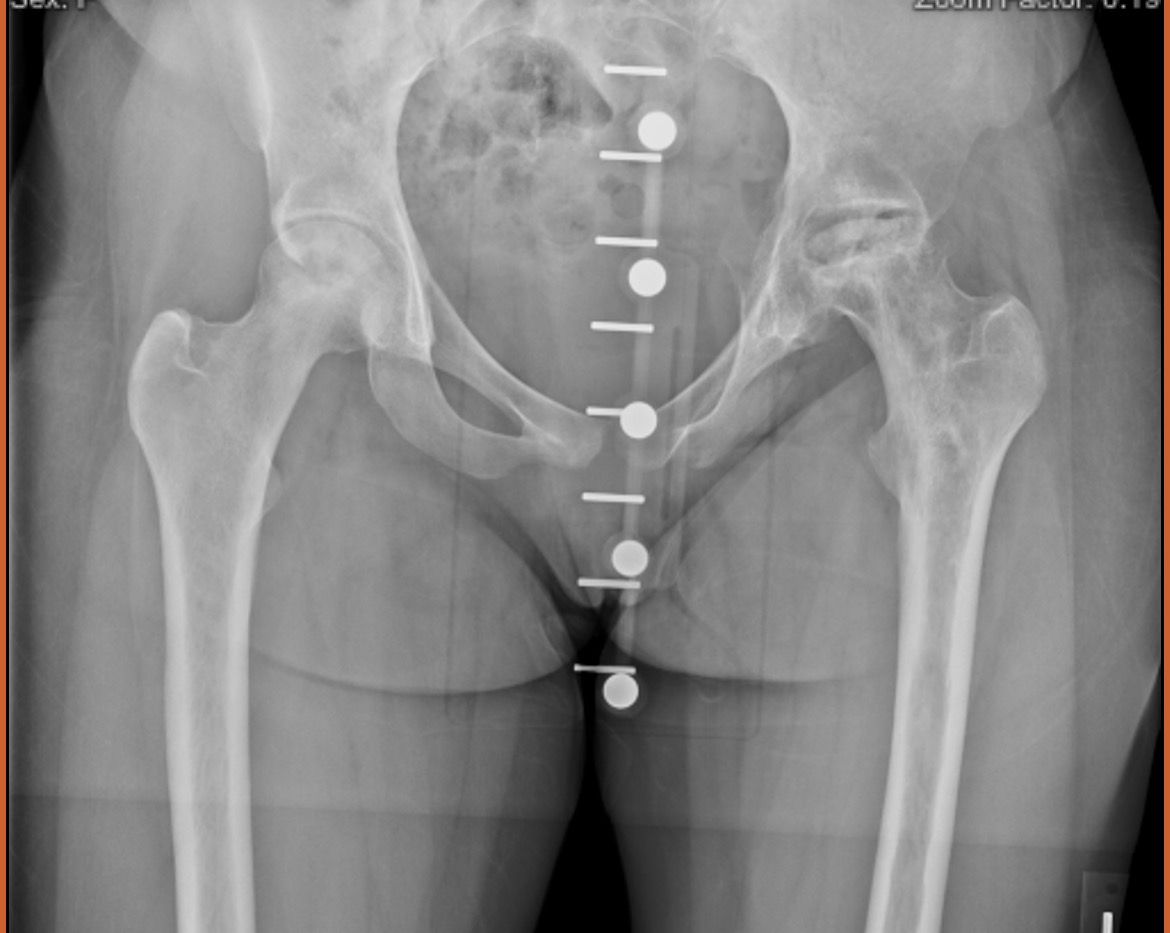

I’m reaching out during a very difficult season in my life. I’m a 22 year old who’s been living with sickle cell disease, and last February, I had to undergo a hip replacement due to complications from my condition. I’ve been working since i was 15 years old but because of my health, I haven’t been able to work for over a year now.